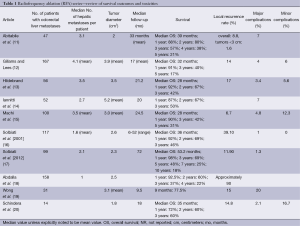

For small hepatocellular carcinomas, the results of RFA approach those of surgical resection with respect to recurrence, time to progression, and overall survival. For colorectal liver metastases, multiple retrospective case matched comparisons as well as meta-analyses are available, which compare surgical resection to RFA (6-8). An increased incidence of recurrence in the treated lesion (5-13%), decreased time to progression, and decreased median survival (1-year, –85%; 3-year, –36%, 5-year, –24%) are reported in patients undergoing RFA compared to surgical resection (7). In well-selected patients with 3 or fewer lesions less than 3 cm in diameter, 5-year survivals of up to 33% are reported (9). In patients who are not surgical candidates, RFA remains a valuable tool. It is increasingly used in conjunction with surgical resection to increase the number of surgical candidates. A study by Livraghi in 2003 demonstrated that RFA followed by incomplete ablation or recurrence in the ablative bed did not negatively affect subsequent surgical resection (10). The most important factor for local recurrence after RFA is tumor size, and larger lesions are at higher risk for local failure (Table 1).